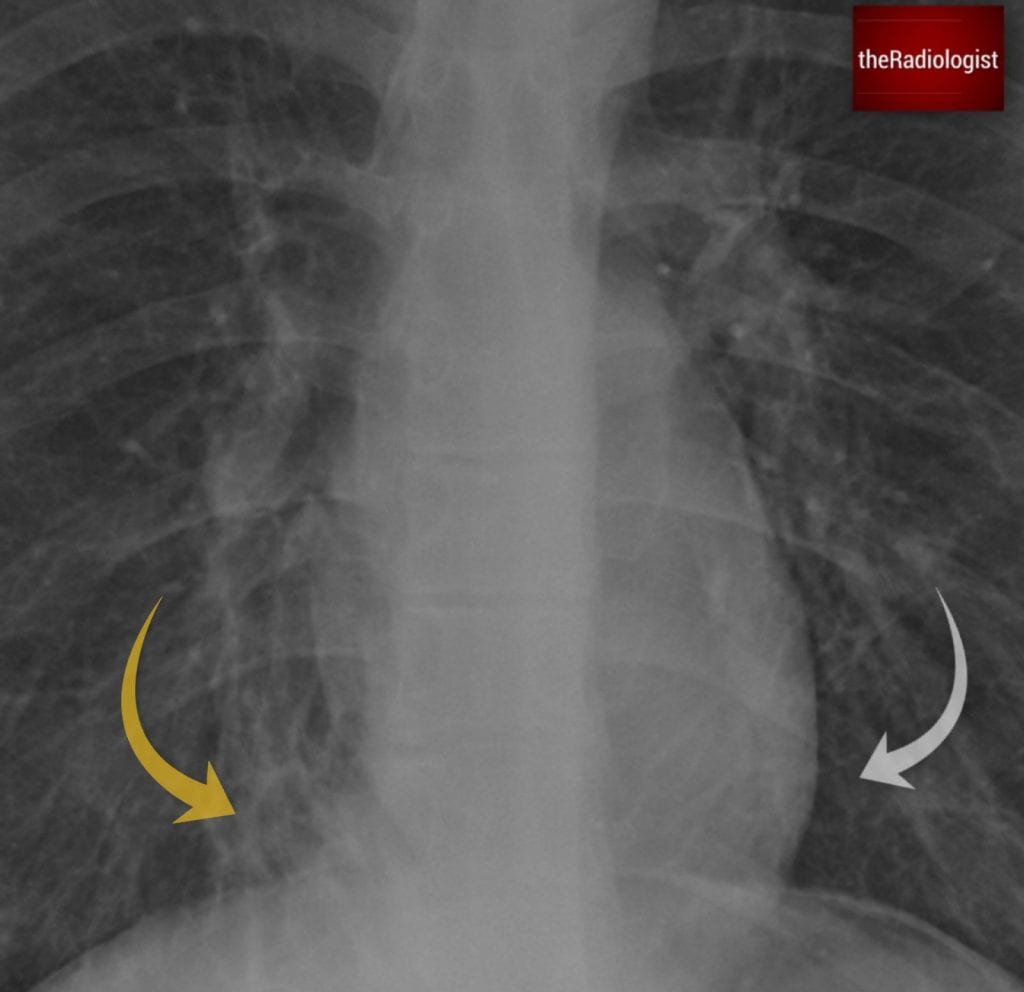

Compare the area of lung adjacent to the right (yellow arrow) and left heart border (white arrow) and you will see the region adjacent to the right heart border appears abnormal. Look closely and you will see a ‘ring shadow’ raising the possibility of bronchiectasis.

Now that we’ve analysed the CT, let’s go back to the original chest X-ray. The ring shadows represented dilated airways seen end-on and are something to look out for on X-Ray.

The area of abnormality on the chest X-Ray correlates with the area of cystic bronchiectasis seen on CT.